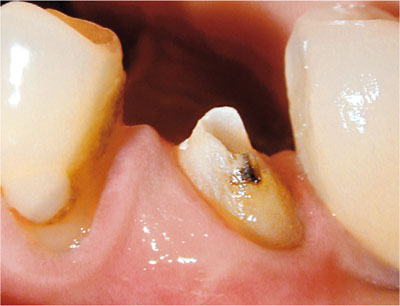

Ideally, there should be a minimum of 2 mm of sound supragingival tooth tissue around the circumference of the tooth for subsequent restoration with a cuspal coverage restoration (Fig 1-2). If there is any doubt in respect to the prosthodontic restorability (see Chapter 8), the existing restoration should be completely removed to reveal the extent and location of residual sound tooth tissue (Fig 1-3). It is essential to inform the patient and secure their consent prior to embarking on this type of exploratory treatment. If the tooth is found to be unrestorable, an informed decision should be made to extract rather than attempt a heroic restoration.

Fig 1-2